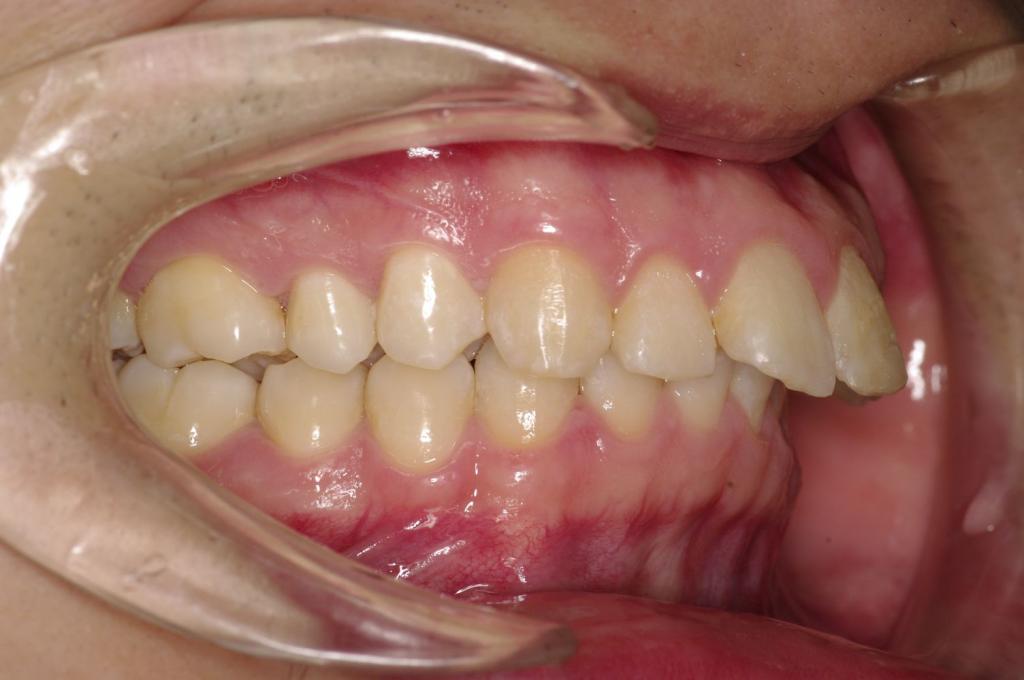

前歯、出っ歯・開咬の矯正治療

(治療期間、治療前後写真、治療方法、費用)WORKS